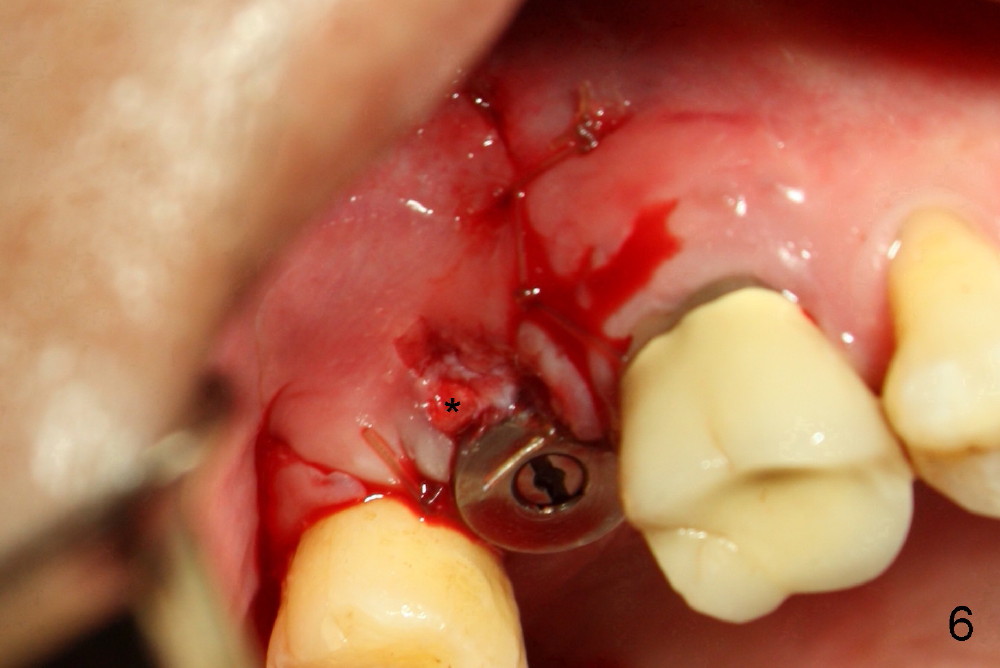

The implant threads (T) are exposed buccally. A flap is raised (Fig.5) with periosteum underscored. After placement of Osteogen (HA 300-500 µm) and Collaform (a collagen membrane, Fig.6*), the flap is sutured. There is no intra- or post-op nasal hemorrhage. The wound heals (Fig.7 (5 days postop), 8 (18 days)). It is apparent that the membrane (Fig.7 *) is replaced by the healing gingiva (Fig.8 *). Three months postop, the buccal gingiva looks normal (Fig.9) around the stable implant (Fig.10).